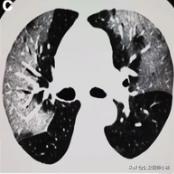

恶化

如果治疗不及时,或者免疫力无法抵御病毒,则很可能威胁生命,发展为白肺。

白肺,肺部恶化

当然白肺在仅仅发生在极少数弥漫性肺部损伤且涉及多个肺叶的危重型患者。

在此阶段,患者肺通气功能严重受损需要持续性吸氧,甚至需要进行体外膜氧合(ECMO)俗称人工肺。